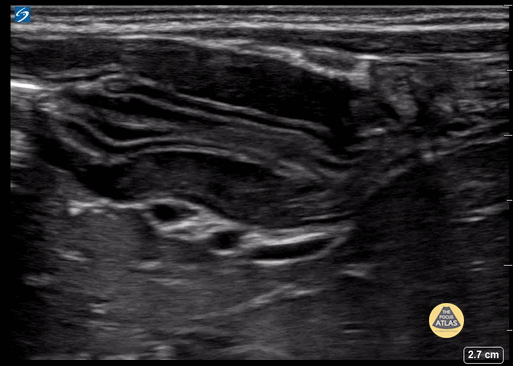

Peds-Gastrointestinal - Pyloric Stenosis 2 (1/2)

2+ weeks projectile vomiting. Extreme lab abnormalities including Cl 67. CG4: 7.57/67/34/60, base excess >30, lactate 3.23. The pyloric channel is elongated, thickened, and has an absence of trans-pyloric flow. Contributor: Matthew Moake, MD PhD